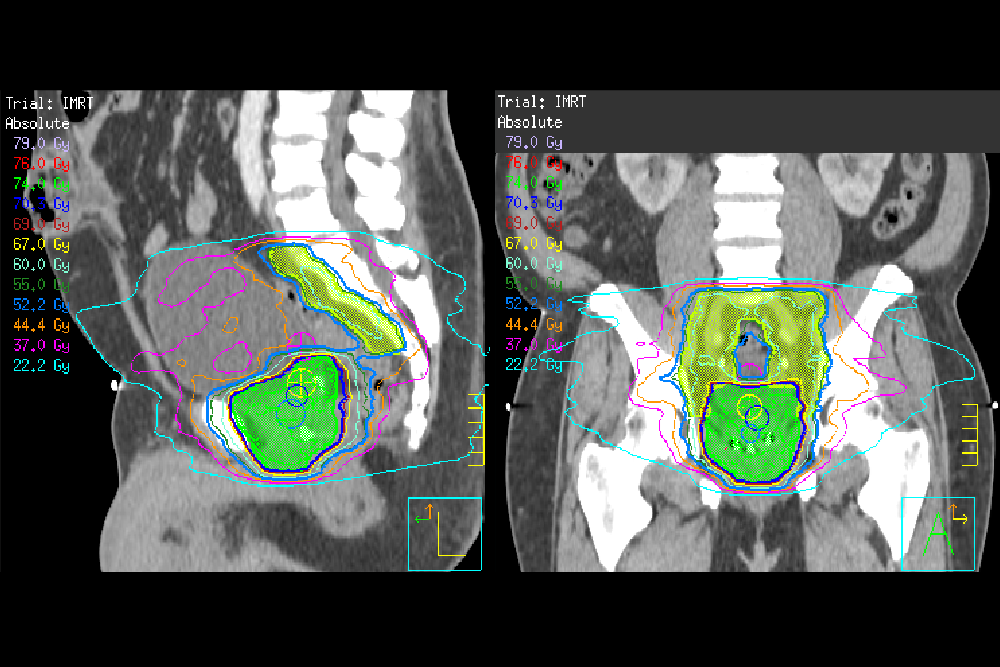

Free eLearning: EBRT and follow-up for prostate cancer

• recall the different forms of radiation-based treatments for the radical treatment of prostate cancer

• describe the different clinical scenarios in which each radiation-based treatment may be useful

• assess the radiobiological implications of the different methods of dose delivery and the effect of changing the dose, and fractionation on the tumour and on normal tissues